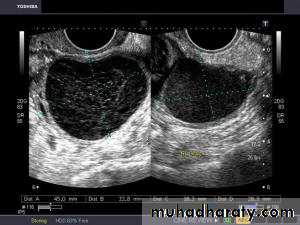

• POLYCYSTIC OVARY SYNDROME

Images from women with differing expressions of the four major subtypes of the metabolic syndrome associated with polycystic ovary syndrome (A–D). The images exhibit quite differing ultrasonographic appearances in the size and distribution of follicles within PCOS ovaries. A recent corpus luteum is clearly visible in the ovary in panel (D).